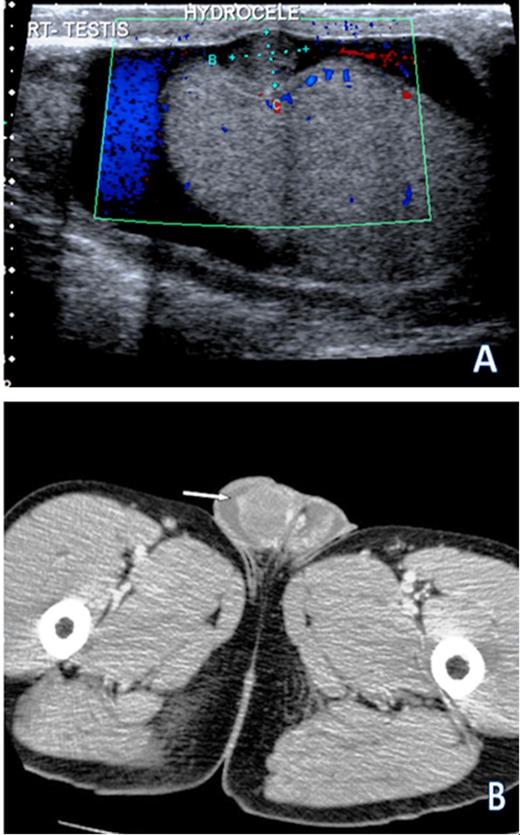

Ultrasound demonstrated multifocal echogenic lesions with intrinsic vascularity confined to the tunica vaginalis. These findings were felt to be highly suspicious for mesothelioma (Figure 1). Subsequently the patient had a staging CT scan of the thorax, abdomen and pelvis and this demonstrated no evidence of metastatic disease.

(A) Ultrasound scan demonstrating the largest of multiple small nodules studding into the right tunica vaginalis in addition to a hydrocele. Doppler interrogation suggests that this nodule has parasitized blood flow from the testis. (B) CT scan demonstrating bilateral hydroceles with enhancing nodularity of the tunica vaginalis on the right (arrow)